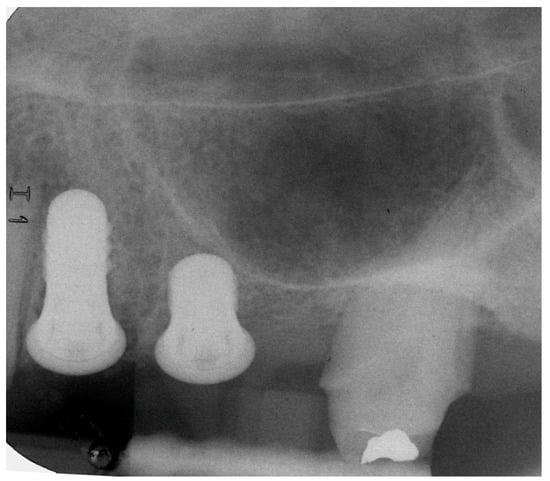

4.1. Marginal Bone Level (MBL)

4.2. Bone tissue remodeling (MBL change)

| Implant | MBL (mm). Mean ± Standard Deviation | ||

|---|---|---|---|

| Baseline | 12 Months | 24 Months | |

| 8 mm | 1.04 ± 0.78 | 1.27 ± 0.85 | 0.87 ± 0.41 |

| 4 mm | 0.89 ± 0.88 | 1.37 ± 1.01 | 1.14 ± 0.95 |

| p-Value (Mann-Whitney) | 0.739 | 0.980 | 1.000 |

| Implant | MBL Change. Mean ± Standard Deviation (mm) | |

|---|---|---|

| 12 Months | 24 Months | |

| 8-mm | −0.13 ± 0.30 | −0.24 ± 0.23 |

| 4-mm | −0.39 ± 0.60 | −0.33 ± 0.65 |

| p-Value (Mann–Whitney) | 0.442 | 1.000 |